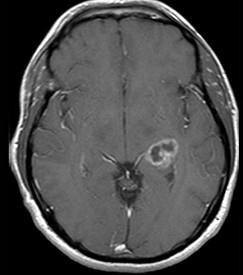

男,53岁,头晕,偏盲,请结合影像图像选择最可能的诊断()A.脑脓肿B.室管膜瘤C.脑膜炎D.脑膜瘤E.多形性恶性胶质瘤

问题 男,53岁,头晕,偏盲,请结合影像图像选择最可能的诊断()

选项 A.脑脓肿 B.室管膜瘤 C.脑膜炎 D.脑膜瘤 E.多形性恶性胶质瘤

答案 E